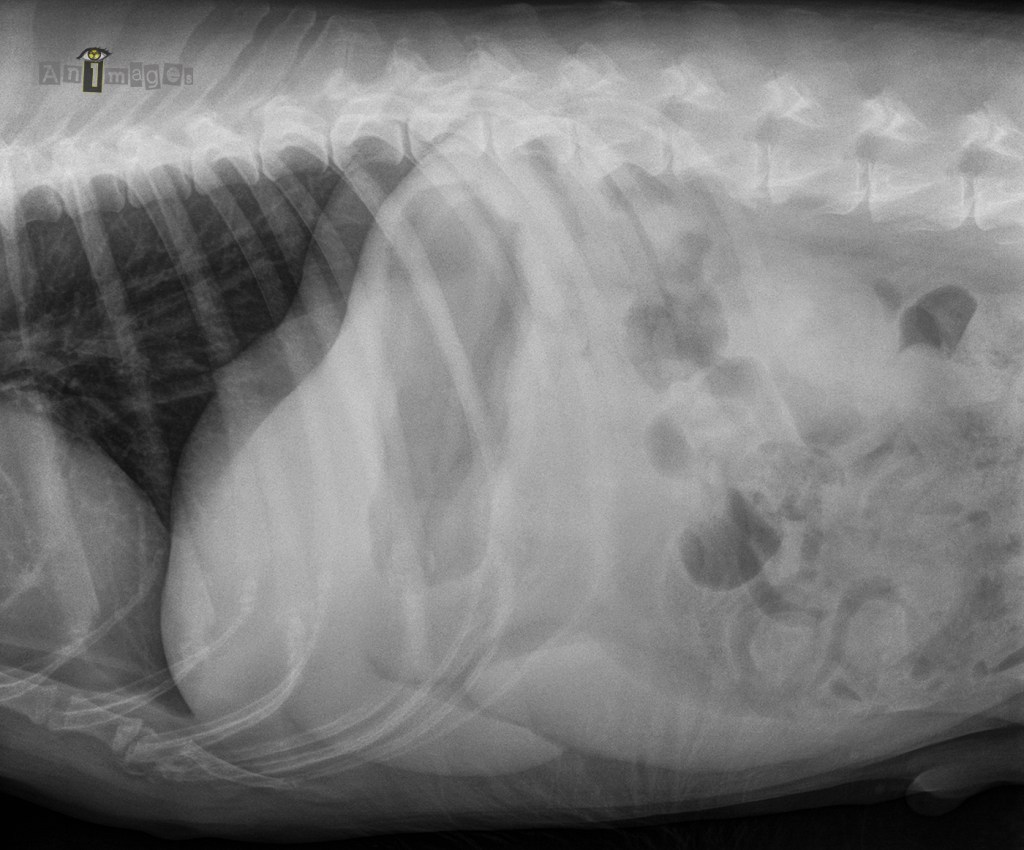

Latérale droite – crâniale